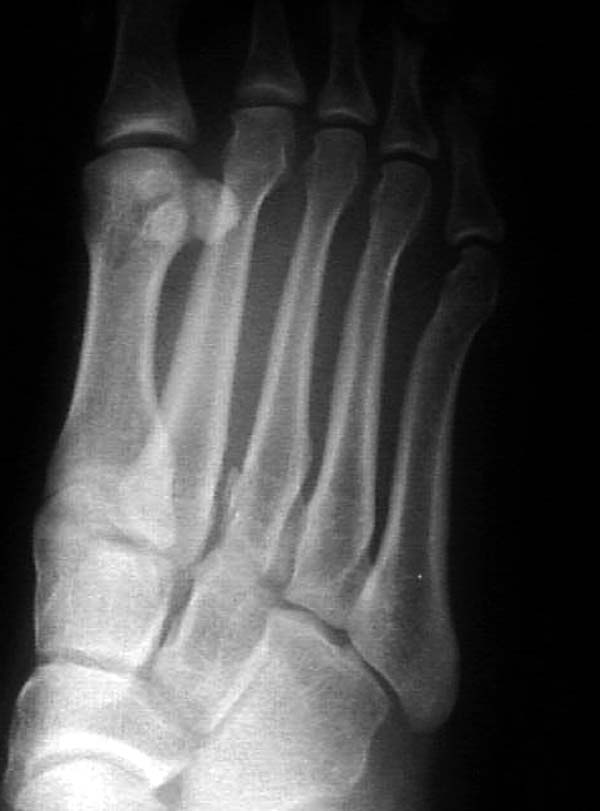

По снимкам нельзя исключить разрыв связки Лисфранка (связки между медиальной клиновидной костью и основанием второй плюсневой). Помогает в диагностике клиника (наличие изолированной гематомы на подошвенной поверхности стопы) и МРТ картина. Если связка повреждена - необходимо оперативное лечение.

По первому снимку, не видя больного, мог бы заподозрить перелом основания 3-й плюсневой кости. Поэтому избрал бы тактику консервативного лечения, как при переломе плюсневых костей без смещения!

Полностью поддерживаю. Наверное стоит проверить локализацию боли осевой нагрузкой на каждый палец отдельно. Если 3 реагирует максимально - вопрососв быть не должно.